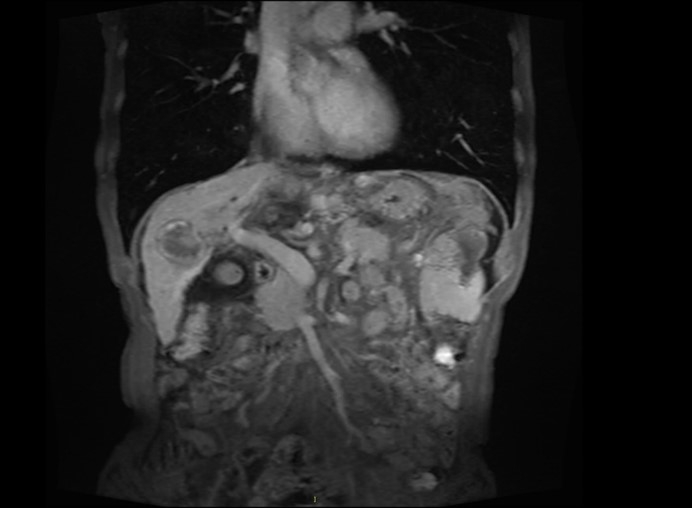

服药1月影像学检查-腹部MR:

检查时间:2017 -8

影像图谱:肝右叶活性灶体积明显缩小

肝癌介入术后,增强后未见明显异常强化灶

肝硬化,脾大,脾静脉、食管胃底静脉迂曲扩张。

脾内多发梗死灶。

肝周、脾周少许积液。

胆囊炎,胆囊周围积液。

肝脏小囊肿。左肾小囊肿。